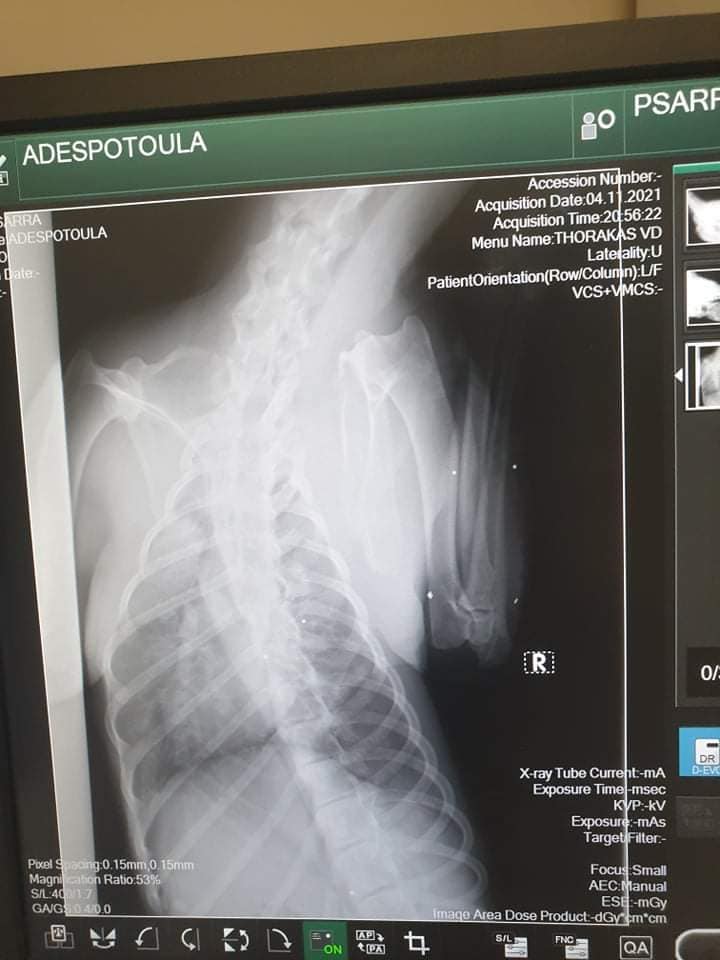

Το ζώο χειρουργήθηκε στις 9 Νοεμβρίου καθώς μεταξύ άλλων είχε και πυομήτρα. Οι ακτινογραφίες, που έβγαλε στην κλινική έδειξαν και τα πολλά σκάγια στο κορμί του – δηλαδή έχει πυροβοληθεί από κυνηγό – καθώς και το κάταγμα κνήμης και περόνης στο πόδι, το οποίο αντιμετωπίστηκε με νάρθηκα, αλλά και ο υγρό στον πνεύμονα (το όποιο αφαιρέθηκε με παρακέντηση). Είχε επίσης και εσωτερική αιμορραγία στην κοιλιακή χώρα.